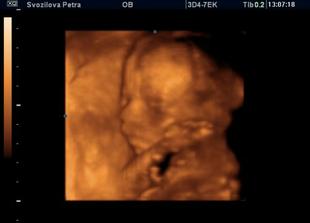

Nase miminko